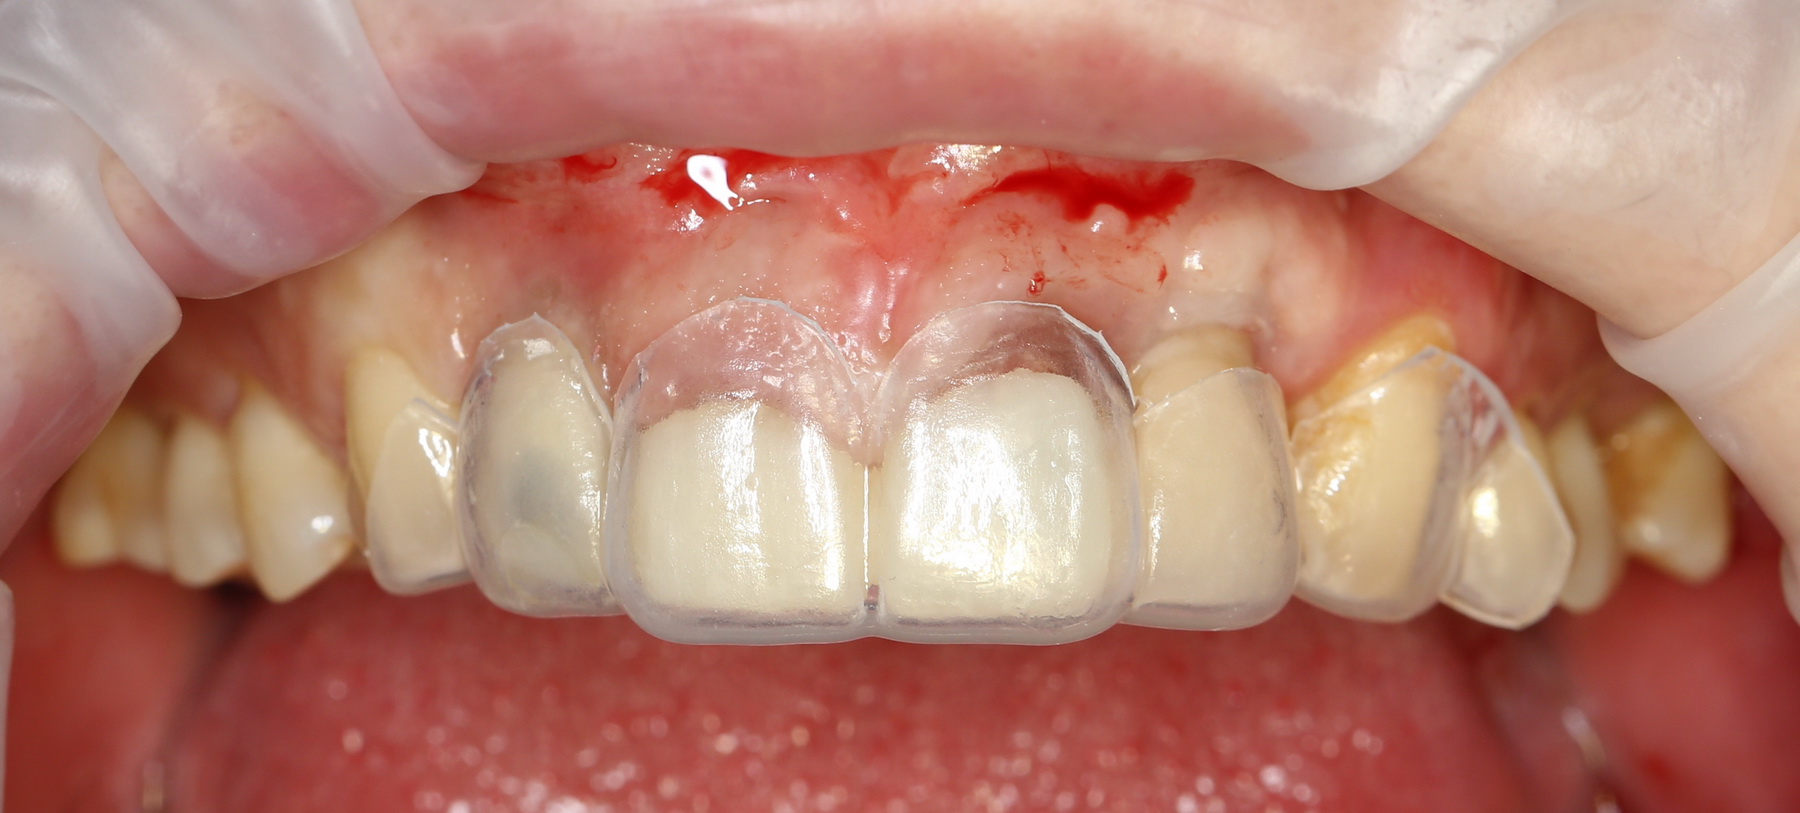

Для этого Давид делает wax-up — восковое моделирование группы зубов. По нему изготавливает каппу для контурирования зубов:

После чего я это самое контурирование и делаю:

а когда десна более-менее заживает:

он меняет временные коронки на более естественные. С этого момента мы уже можем оценить первые результаты нашей работы: